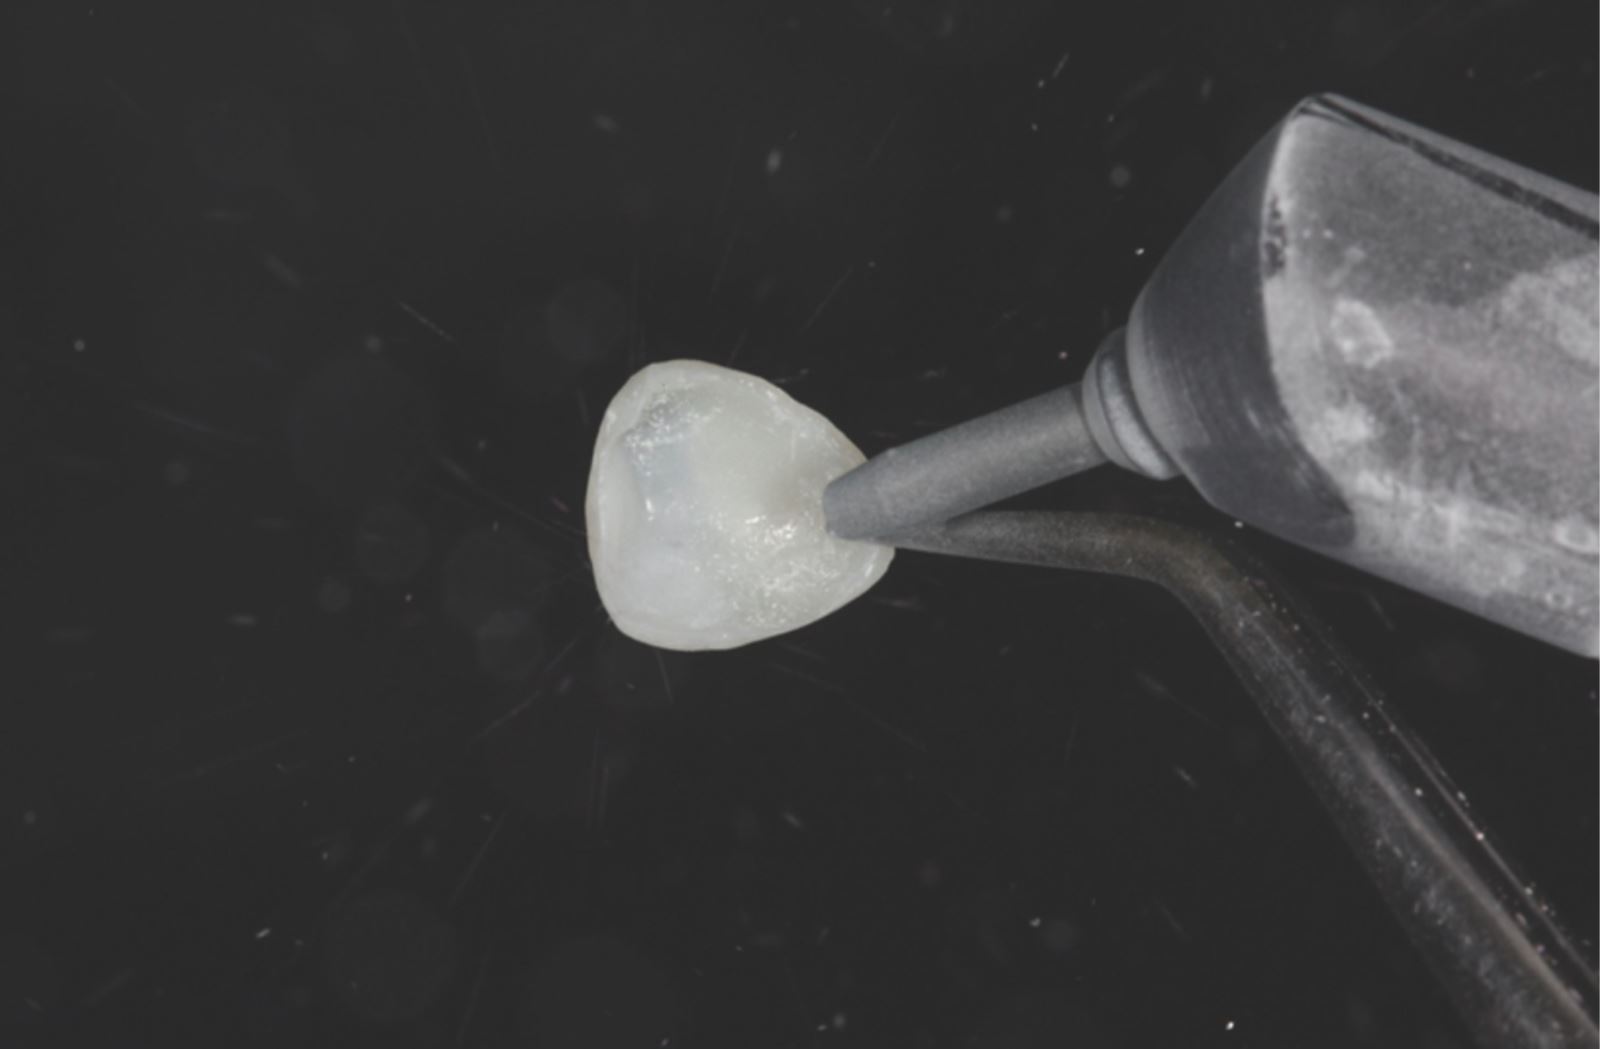

Sejmutí kompozitních fazet:

Kompozitní fazety byly sejmuty.

Leštění a příprava na cementaci:

Fazety byly konturovány a vyleštěny pomocí lešticí sady Jiffy™ Natural, čímž byly připraveny k cementaci.

Úprava vnitřního povrchu:

Vnitřní povrch fazety byl pískován. Alternativně lze pro tento krok použít 35% kyselinu fosforečnou Ultra-Etch™.

Nanesení adheziva:

Vnitřní povrch fazety byl potažen adhezivem Peak™ Universal Bond.

Ztenčení a polymerace adheziva:

Adhezivum bylo ztenčeno proudem vzduchu a následně polymerováno světlem VALO™ X po dobu tří sekund v režimu Xtra Power.